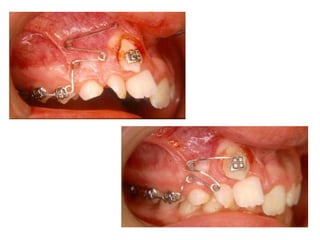

TRANSPOSIÇÃO TOTAL - CANINO COM INCISIVO LATERAL MANOBRAS PARA CORREÇÃO DA ROTA DE ERUPÇÃO